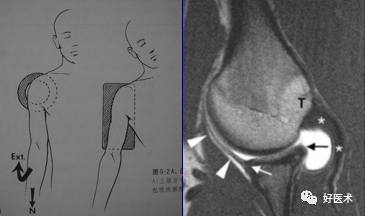

盂唇韧带复合体最佳显示体位(举过头顶并外旋、外展位)ABER position

ABER位(前臂外旋外展位):检出关节盂及韧带病变